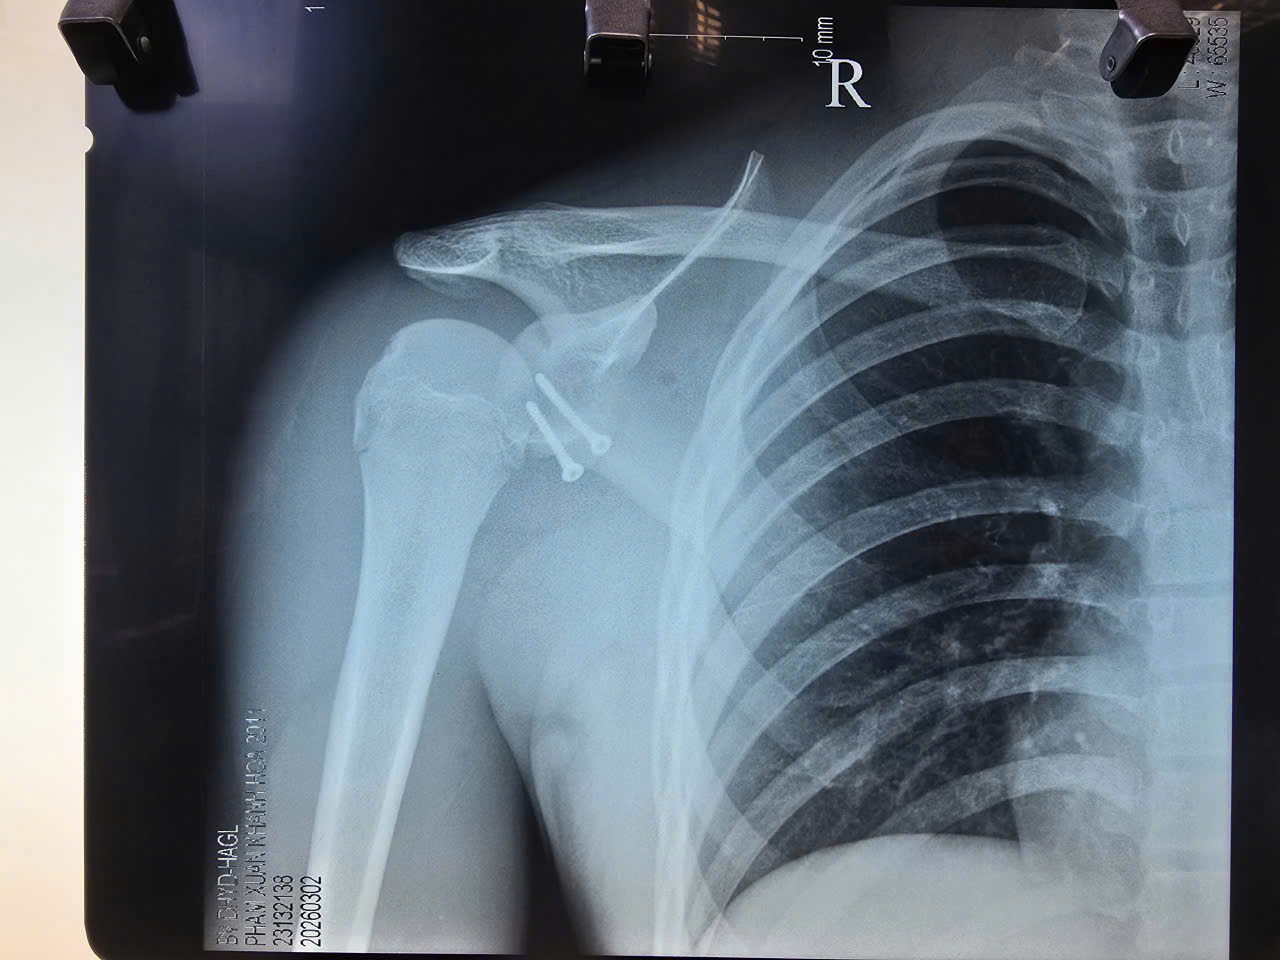

Mới đây, các bác sĩ của bệnh viện tiếp tục thực hiện ca phẫu thuật thành công cho một cầu thủ U15 đến từ Khánh Hòa bị trật khớp vai tái diễn nhiều lần.

Ca mổ được tiến hành theo phương pháp Latarjet, với mục tiêu tái tạo lại sự vững chắc của khớp vai, hạn chế nguy cơ trật lại trong tương lai. Sau phẫu thuật, khớp vai của bệnh nhân được ổn định tốt, tạo điều kiện thuận lợi để vận động viên trẻ sớm phục hồi chức năng và quay lại tập luyện.

Cầu thủ U15 này vừa thoát “cơn ác mộng” trật khớp vai tái diễn nhờ ca mổ tại BV Đại học Y Dược – Hoàng Anh Gia Lai